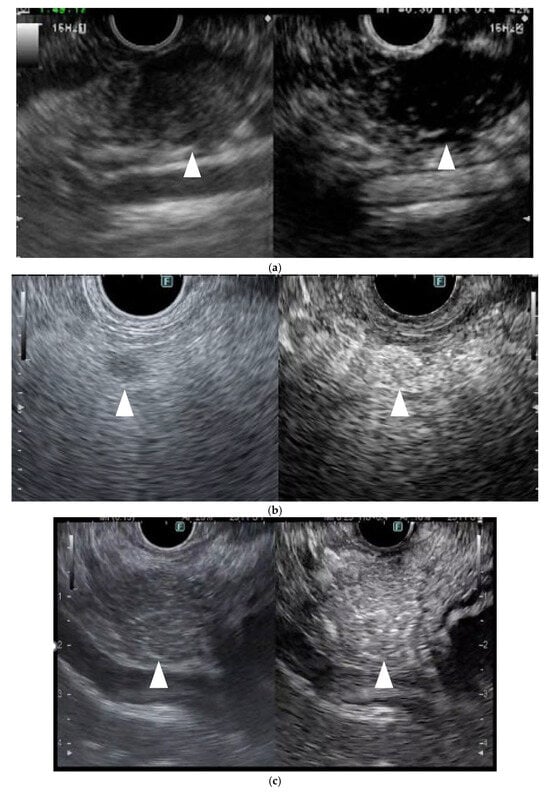

In CH-EUS, pancreatic cancers are typically depicted as hypovascular, inflammatory masses as isovascular, and NETs as hypervascular compared with the surrounding pancreatic tissues. In the previous report, 104 of 109 (94%) PCs were hypovascular, eight of 11 (72%) were inflammatory masses, eight of nine (89%) autoimmune pancreatitis were isovascular, and five of eight (63%) NETs were hypervascular (Figure 4) [22]. They compared the pathology image to the early phase contrast pattern and showed that the pathology in the hypovascular pattern showed heterogeneous tumor cells, necrotic tissue, fibrous tissue, and few vessels, and in the isovascular pattern, homogeneous tumor cells, abundant vessels, and no necrotic or fibrous tissue were found.

In a meta-analysis comparing CH-EUS in 719 patients and conventional EUS in 723 patients, the sensitivity, specificity, diagnostic odds ratio, and AUC were 93%, 80%, 57.9, and 0.96 for CH-EUS and 86%, 59%, 8.3, and 0.80 for conventional EUS. For the diagnosis of PC, CH-EUS was 2.98 times more accurate than conventional EUS [23].

For small PCs (11–20 mm), the sensitivity, specificity, and accuracy of CH-EUS, CT, and MRI are 95%, 83%, and 94%; 78%, 83%, and 79%; and 73%, 33%, and 68%, respectively; therefore, the diagnostic ability of CH-EUS is significantly superior to that of CT and MRI. Moreover, the sensitivity, specificity, and accuracy of CH-EUS, MDCT, and MRI for the detection of PC ≤ 10 mm is 70%, 100%, and 77%; 20%, 100%, and 38%; and 50%, 100%, and 62%, respectively [24]. Therefore, CH-EUS is indispensable for the diagnosis of PCs.

In terms of malignant potential, NENs are considered to be aggressive if morphologic/histologic findings are consistent with metastatic disease (i.e., adjacent organ involvement, lymph node involvement, distant organ metastasis), and/or histologic findings suggest a G3 tumor (Ki67 > 20%). The diagnostic ability for tumor aggressiveness with CH-EUS was 96% in sensitivity, 82% in specificity, and 86% in accuracy, respectively [25]. Therefore, CH-EUS contributes not only to aid diagnosis but also enables the estimation of the malignant potential of NENs.

Figure 4. Typical contrast-enhanced harmonic EUS (CH-EUS) images of a pancreatic lesion. (a) Representative example of a pancreatic cancer. (Left) B mode EUS detected a pancreatic lesion as an irregular, heterogeneous, and hypoechoic lesion (arrowhead). (Right) CH-EUS shows the pancreatic lesion (arrowhead) as hypovascular compared with the surrounding pancreatic tissue. (b) Representative example of a neuroendocrine neoplasm. (Left) B mode EUS detected a round hypoechoic lesion (arrowhead) pancreatic lesion. (Right) CH-EUS showed the pancreatic lesion to be hypervascular (arrowhead) compared with the surrounding pancreatic tissue. (c) Representative example of an inflammatory mass. (Left) B mode EUS detected a pancreatic lesion as a low echoic mass (arrowhead). (Right) CH-EUS showed that the pancreatic lesion was isovascular (arrowhead) compared with the surrounding pancreatic tissue.